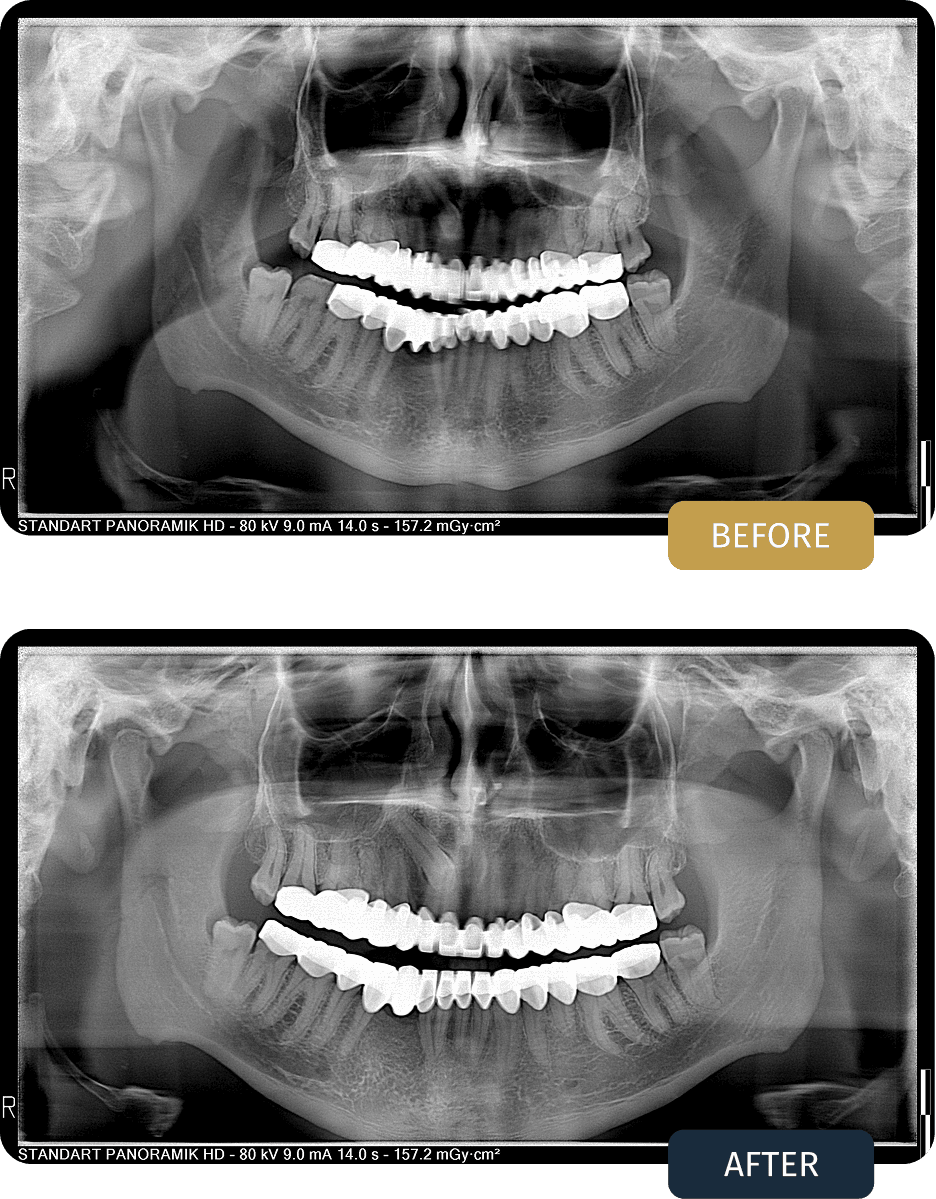

Joshua originally completed comprehensive crown treatment with us in March 2023, receiving a total of twenty seven crowns as part of his smile rehabilitation.

During the aftercare appointment, clinical examination confirmed that the crowns remained well integrated, functional, and stable overall.

One crown had become detached, which can occasionally occur over time due to natural bite forces and daily wear. This was addressed promptly during the visit, with the crown carefully refitted and bite alignment checked to ensure continued comfort and long term stability.